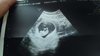

Wszystko w porządku, serduszko bije pięknie i dziecko uroslo. Jestem szczęśliwa ;) a ja mimo nudności i wymiotów przebrałam sobie ponad 3 kg od początku ciąży. .. :D

Załączniki

• received_1745860678835399.jpeg